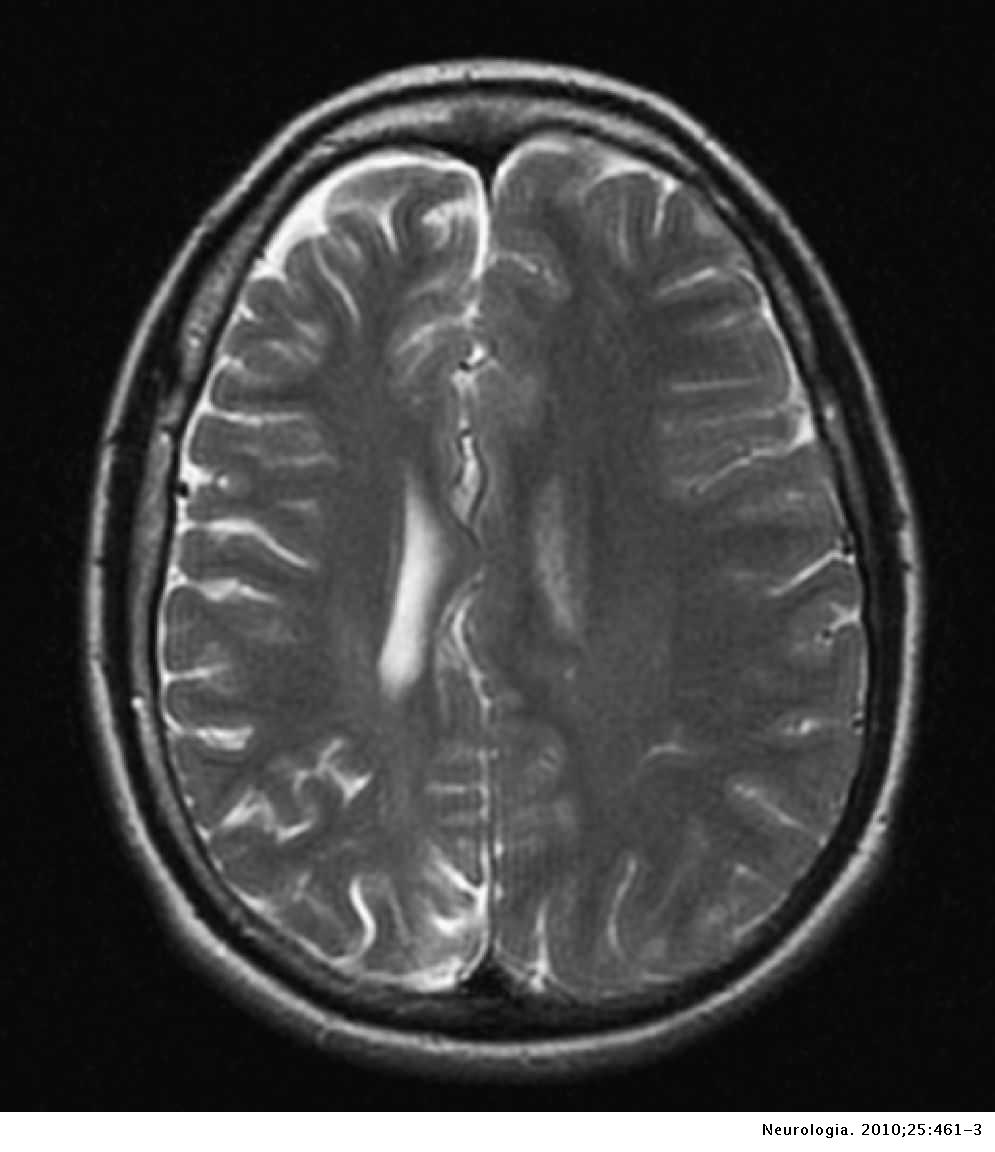

Engineer Team : RESONANCIA MAGNETICA Magnetic Resonance Imaging – Clinical Images Hallazgos por resonancia magnética cerebral de nuestro paciente. M, 21 … Imágenes por resonancia magnética anormales como predictoras de mal … Imágenes por resonancia magnética anormales como predictoras de mal … Lesiones en resonancia magnética (RM) del encéfalo y la médula espinal … Pin en Resonancia Magnética del Encéfalo A) Resonancia magnética cerebral (RMC) mostrando infartos en … Caso 1: Edema cerebral visualizado mediante RM. (A) Secuencia T1 plano … Rascacielos dormir pasta tac y resonancia diferencias retrasar … Pin on Apuntes de Enfermería y T.C.A.E Resonancia magnética cerebral secuencia T2, que muestra lesión … Meningitis aguda en la enfermedad de Behçet | Reumatología Clínica Resonancia magnética coronal normal del cerebro Fotografía de stock – Alamy Imágenes de resonancia magnética, la imagen de la cabeza en diferentes … Resonancia magnética cerebral A) protocolo T1 sagital (Caso 1). Se … Resonancia magnética cerebral. Secuencia T1 corte sagital. Atrofia … Resonancia magnética de cerebro, cortes axiales, secuencias T2. Señal … Resonancia magnética de cráneo. A y B) Cortes axiales FLAIR … Resonancia magnética (RM) de cerebro, corte axial ponderado en T2: la … RM cerebral: Interpretación paso a paso | Kenhub Resonancia magnética de cerebro, cortes axiales, secuencias T2. Señal … De Resonancia Magnética De Cerebro Foto de archivo – Imagen de arteria … Top 107+ Imagenes de resonancia cerebral normal – Destinomexico.mx -Imagen por resonancia magnética del cerebro. a) Cortes sagital y axial … resonanCia magnétiCa Cerebral donde se observa hiperintensidad a nivel … MRI (Imagen de resonancia magnética) – Tomografía computarizada de la … Meningioma – NCI Imágenes por resonancia magnética coloreadas del cerebro sano del … Resonancia magnética cerebral en secuencia FLAIR, que muestra lesiones … Contraste resonancia magnetica cerebral – senturinthegreen Relación de los espacios de Virchow-Robin con la enfermedad de … Gliomatosis cerebral – Instituto Nacional del Cáncer Pin en Neurology. Recomendaciones para la utilización e interpretación de los estudios de … Fotografía De La Proyección De Imagen De Resonancia Magnética Del … atmósfera Dirigir Cumplir anatomia resonancia magnetica Desarrollar … Pin en #MEDICINA,#SALUD Resonancia magnética de la nasofaringe De Resonancia Magnética De Cerebro Foto de archivo – Imagen de polilla … Atrofia cortical global de predominio parietal en la Resonancia … Resonancia magnética cerebral | Download Scientific Diagram Neuroblog: Resonancia magnética cerebral en la trombosis crónica de … De Resonancia Magnética De Cerebro Imagen de archivo – Imagen de … ¿Cuáles son los riesgos de la resonancia magnética? – Integra Salud … Resonancia magnética cerebral al decimocuarto día de ingreso: área … Resonancia magnética. Corte axial mostrando área infartada en el … Resonancia magnética cerebral del paciente AV evidenciando lesiones en … -Ressonância magnética de encéfalo mostrando múltiplas imagens … Resonancia magnética cerebral secuencia FLAIR (Fluid Attenuated … Resonancia magnética cerebral con protocolo de epilepsia, en sección … Resonancia magnética cerebral en corte sagital. Se observa una evidente … Resonancia magnética craneal en la que se evidencian lesiones … Logran visualizar el cerebro a detalle más completo tras una resonancia … Así decide el cerebro la severidad de un castigo De Resonancia Magnética De Cerebro, Imagen de archivo – Imagen de … A) Resonancia magnética cerebral; Secuencia Tof: oclusión de arteria … Un estudio asocia la ansiedad con la aparición rápida del Alzheimer IMÁGENES DE 18 F-PR04.MZ PET FUSIONADA CON RESONANCIA MAGNÉTICA … Imágenes por resonancia magnética anormales como predictoras de mal … Tumores de la región pineal – Instituto Nacional del Cáncer Epilepsia: una historia de voces y fantasmas | Neurología Contribución de las imágenes de resonancia magnética por tensor de … Resonancia magnética secuencia T2 plano coronal de quiste epidermoide … Resonancia Magnética Cerebral del paciente: a. Aumento de… | Download … Resonancia magnética cerebral 2022 Síndrome de hemiconvulsión-hemiplejía-epilepsia. Seguimiento de un caso … Enfoque Radiologico: La resonancia magnética permite detectar lesiones … Resonancia magnética craneal T1 con contraste que muestra angiomatosis … guidewiz – Blog Resonancia magnética cerebral, secuencia SWI. Ribete hipointenso en la … resonAnCiA mAgnétiCA de ColumnA Con gAdolinio. Corte sAgitAl en t1 de … SEMANA 12: FUNDAMENTOS DE RESONANCIA MAGNÉTICA NUCLEAR. INDICACIONES Y … DIAGNÓSTICO DE ESCLEROSIS MÚLTIP Magnetic resonance imaging of the brain – Alchetron, the free social … Resonancia magnética de órbitas | Instituto Radiológico Dr. E Castillo Alteración de la marcha en un paciente post-trasplante hepático Resonancia magnética cerebral de un paciente sano (Ay B) y paciente que … Utilidad de la resonancia magnética craneal para el diagnóstico de la … Resonancia Magnética Del Cerebro El Tumor Cerebral Foto de stock y más … De Resonancia Magnética De Cerebro Imagen de archivo – Imagen de … ABDALLA RADIOLOGIA: NEURINOMA ACUSTICO Atrofia cortical global de predominio parietal en la Resonancia … Resonancia Magnética : Producción de la imagen MRI Brain Scan — Stock Photo © Bunyos30 #18724051 Mri (imagen de resonancia magnética) Monitor con imagen de captura de … Tomografía computarizada vs resonancia magnética: diferencia y … Tumores Cerebrales – Unidad de Neurocirugía RGS Resonancia magnética de la columna, sección sagital. Observe los discos … La resonancia magnética, una técnica imprescindible en el diagnóstico … Perfusión Cerebral por Resonancia Magnética | ¿Qué es? ¿Necesita Contraste? Resonancia Magnética Cerebro A: resonancia magnética, T2 coronal preoperatoria; se observa lesión en … Resonancia magnética cerebral — Foto de stock © Bunyos30 #27340623 La resonancia magnética se perfila como detector de mentiras | Futuro … Resonancia magnética cerebral en T1 con gadolinio, cortes axial (a … MRI brain : show brain tumor at right parietal lobe of cerebrum — Stock … NEUROIMÁGENES EN ENFERMEDAD DE PARKINSON: ROL DE LA RESONANCIA …